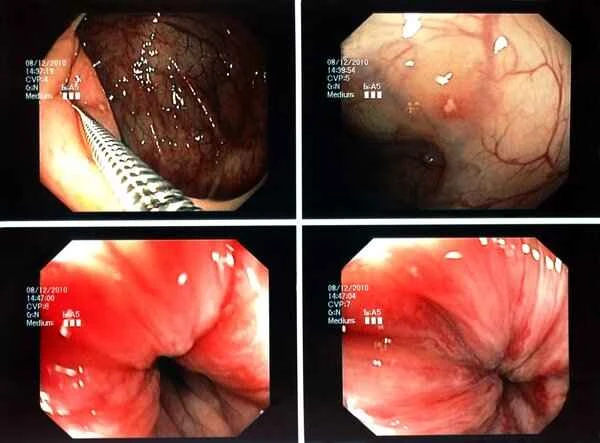

The level of pain after sigmoid colon redundancy surgery varies from person to person and depends on a variety of factors. Sigmoid colon redundancy surgery is a procedure used to treat sigmoid colon redundancy, a condition typically characterized by an excessively long and tortuous sigmoid colon, which can lead to symptoms such as difficulty defecating and abdominal pain. Post-operatively, patients may experience some discomfort or pain due to the direct manipulation of abdominal tissues during the procedure and the body's natural response during recovery. Post-operative pain usually subsides gradually over several days to weeks, but the specific recovery time varies depending on individual differences, including pre-operative health conditions, the surgical method, and post-operative care.